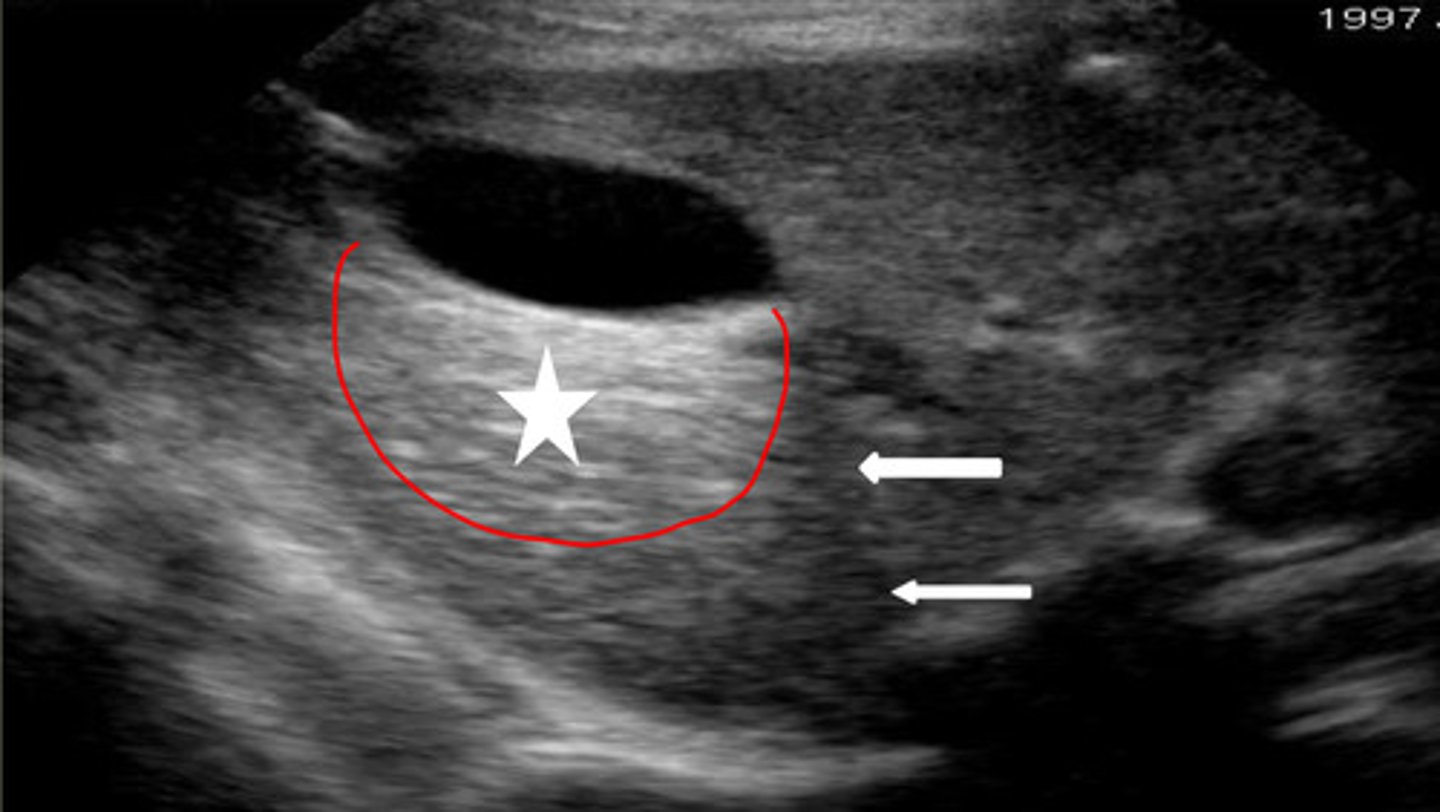

distal enhancement

what artifact is the red circle indicating underneath the gallbladder?

-distal acoustic enhancement

-refraction

what are the two artifacts associated with the gallbladder?

increases echogenicity in liver parenchyma deep to gallbladder

what does distal acoustic enhancement do?

bending artifact at edges of gallbladder, seen at curved surfaces

what is refraction artifact?

star- distal enhancement

arrow- refraction

does the star or arrows show distal enhancement or refraction?